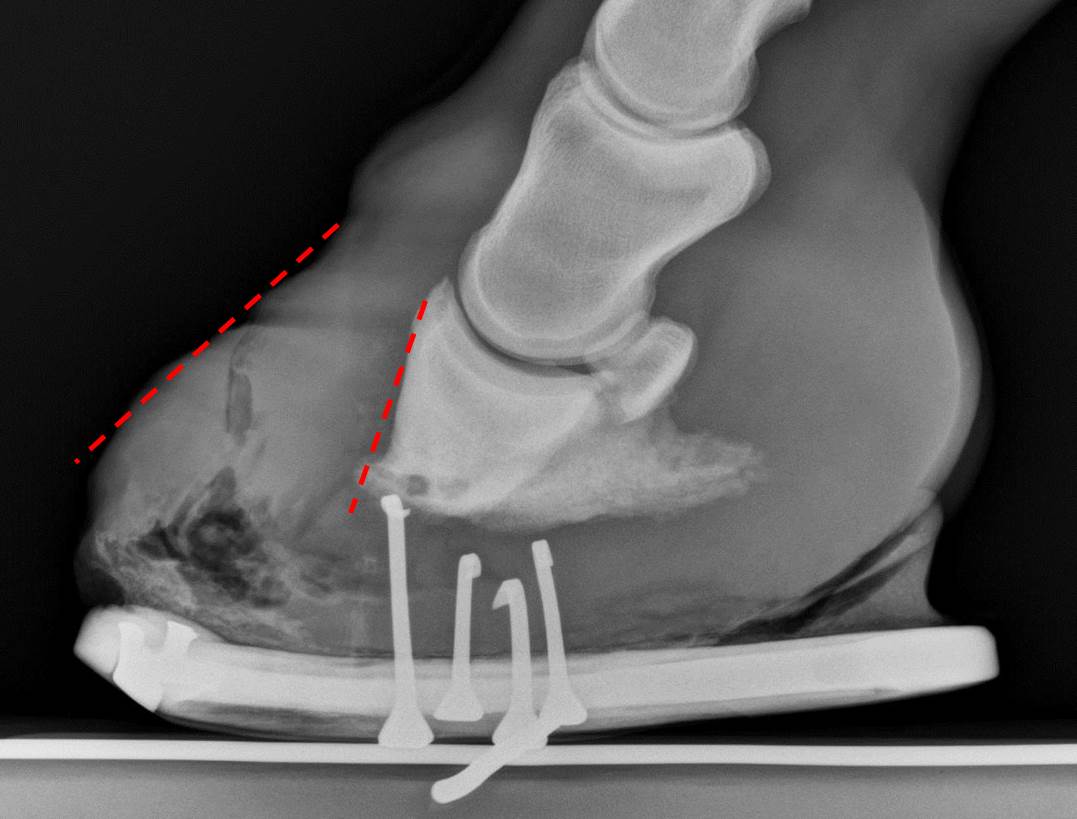

From rockleyfarm.blogspot.com

Rockley Farm What happens when a horse has thin soles and poor hoof Horse Sole Bleeding Sole bruises are a common condition affecting horses. Any time trimming the hoof reveals a bruise, three questions arise: What can we do to help it? Sharp impacts to the bottom of a horse’s hoof cause blood vessels. By the time a hoof bruise is visible on the sole, weeks or months have passed since trauma of some sort—from rocky. Horse Sole Bleeding.